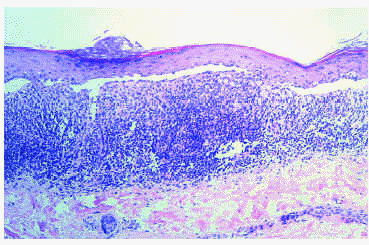

El estudio histopatológico de una biopsia de la lesión de región mamaria mostró hiperqueratosis ortoqueratósica, atrofia epidérmica, degeneración vacuolar focal en la interfase, marcado edema de la dermis papilar, homogeneización del colágeno y un intenso infiltrado linfohistiocitario perivascular en la dermis superficial. Estos hallazgos, que confirmaban el diagnóstico clínico de liquen escleroso, se demostraron también en una biopsia obtenida de las lesiones anogenitales. Por otro lado, en el examen microscópico de una pápula de la región lumbosacra se observaron hallazgos típicos de liquen plano como hiperqueratosis, hipergranulosis, acantosis con crestas interpapilares «en dientes de sierra», degeneración hidrópica intensa de los queratinocitos basales con formación de hendiduras subepidérmicas (espacios de Max Joseph) y un infiltrado linfohistiocitario dérmico en banda (fig. 3).

Fig. 3.--En la dermis papilar se observa intenso infiltrado inflamatorio «en banda». En la epidermis se aprecia ortoqueratosis, hipergranulosis focal y degeneración hidrópica marcada de los queratinocitos basales con formación de hendiduras subepidérmicas (espacios de Max Joseph). (Hematoxilina-eosina, x200.)